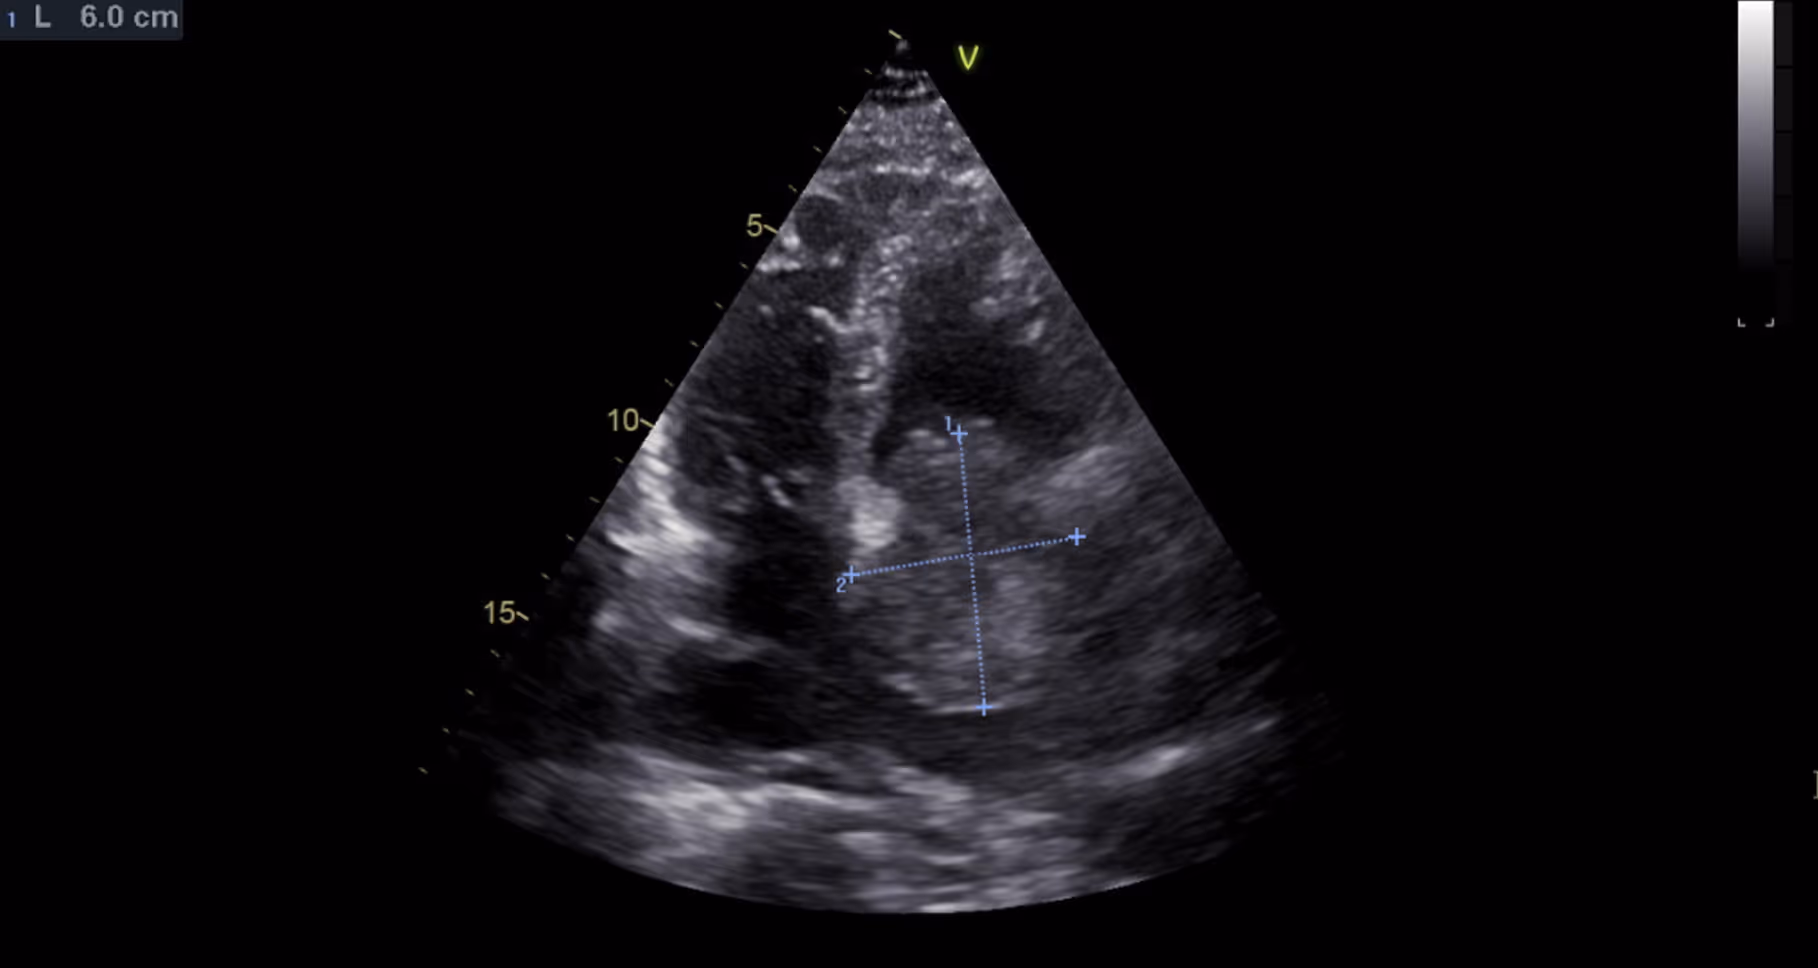

Patient with a Stanford type A aortic dissection

2021-03-08

in

Clinical Cases